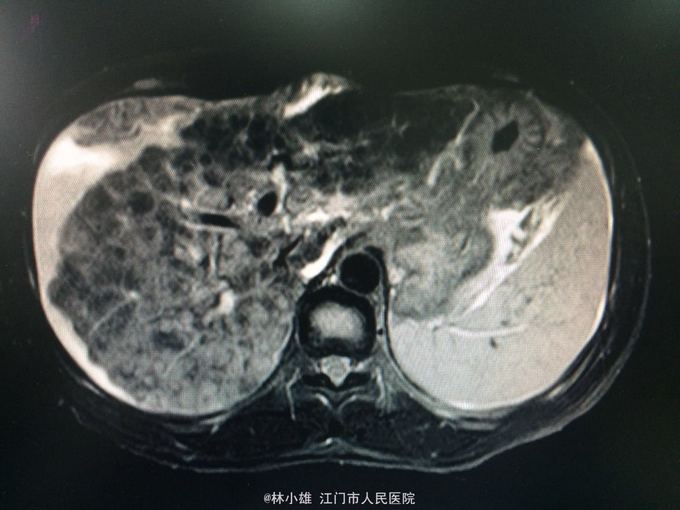

40岁男性,乙肝病史10余年,具体治疗不详,近2月不规律富有恩替卡韦。 腹胀腹痛1月余,身目黄染20天,伴乏力、纳差。 外院就诊查转氨酶、胆红素稍增高,治疗不详。后出现便秘,腹平片示不完全肠梗阻,CT示肝硬化、腹水,HBV DNA5次方。治疗后症状有好转,但仍身目黄染、腹痛,遂入院。

查体:神清,反应稍迟钝,计算力稍下降,皮肤巩膜轻度黄染,肝掌阳性,胸前毛细血管有扩张。腹膨隆,腹肌紧张,右上腹反跳痛。移动性浊音阳性。 辅查:如图。AFP6.12ng/ml,PT 20.5s PTA 46%。

诊断:弥漫性肝癌,乙肝后肝硬化失代偿期:腹膜炎、腹水,I度肝性脑病。 予舒普深抗感染、补白蛋白、护肝、降酶等治疗。请介入科会诊后考虑患者肝癌范围大,已无手术指征。

考虑乙型肝炎后肝癌,现晚期,治疗愈后差。